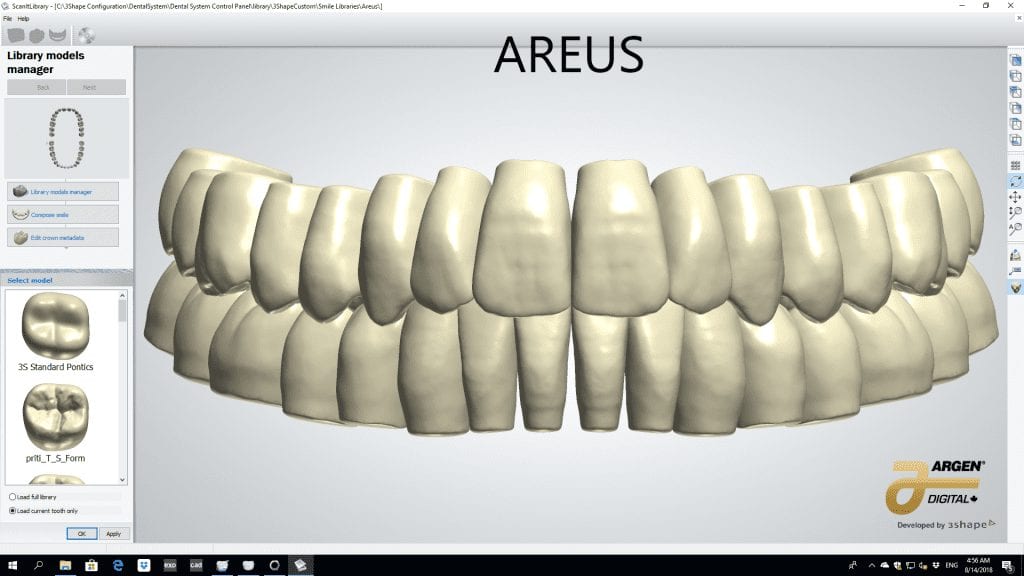

The digital models were then imported into a third party software where a library of tooth morphologies are available for the clinician to choose from.

Once the appropriate library is chosen, the digital wax ups are performed. In the subsequent photos you can see the transparent overlay of the wax-ups to the original position of the existing dentition